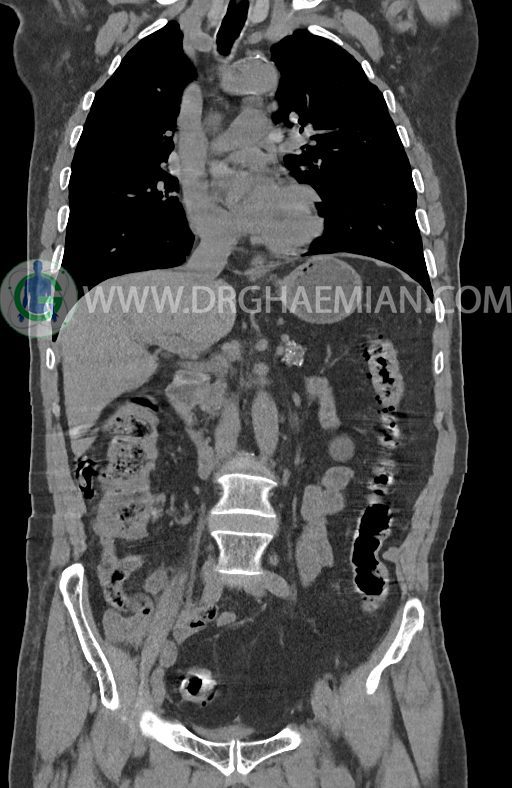

در سی تی اسکن اسپیرال ریه ها و مدیاستن، شکم و لگن با و بدون کنتراست وریدی (مولتی دیدکتور 16 با مقاطع ظریف و بازسازی کرونال) :

–آتروفی نسبی پانکراس همراه با فوکوس های کلسیفیه ی منتشر پارانشیم مطرح کننده ی پانکراتیت مزمن

-CBD بسیار دیلاته (16mm) همراه با دیلاتاسیون مجاری داخل کبدی سنترال بدون شواهد سنگ یا توده در مسیر

–کیست های کورتیکال متعدد هر دو کلیه به بزرگترین قطر 56mm

–پروستات به دیامتر عرضی بزرگ حاوی فوکوس کلسیفیه

–لومباریزاسیون مهره S1